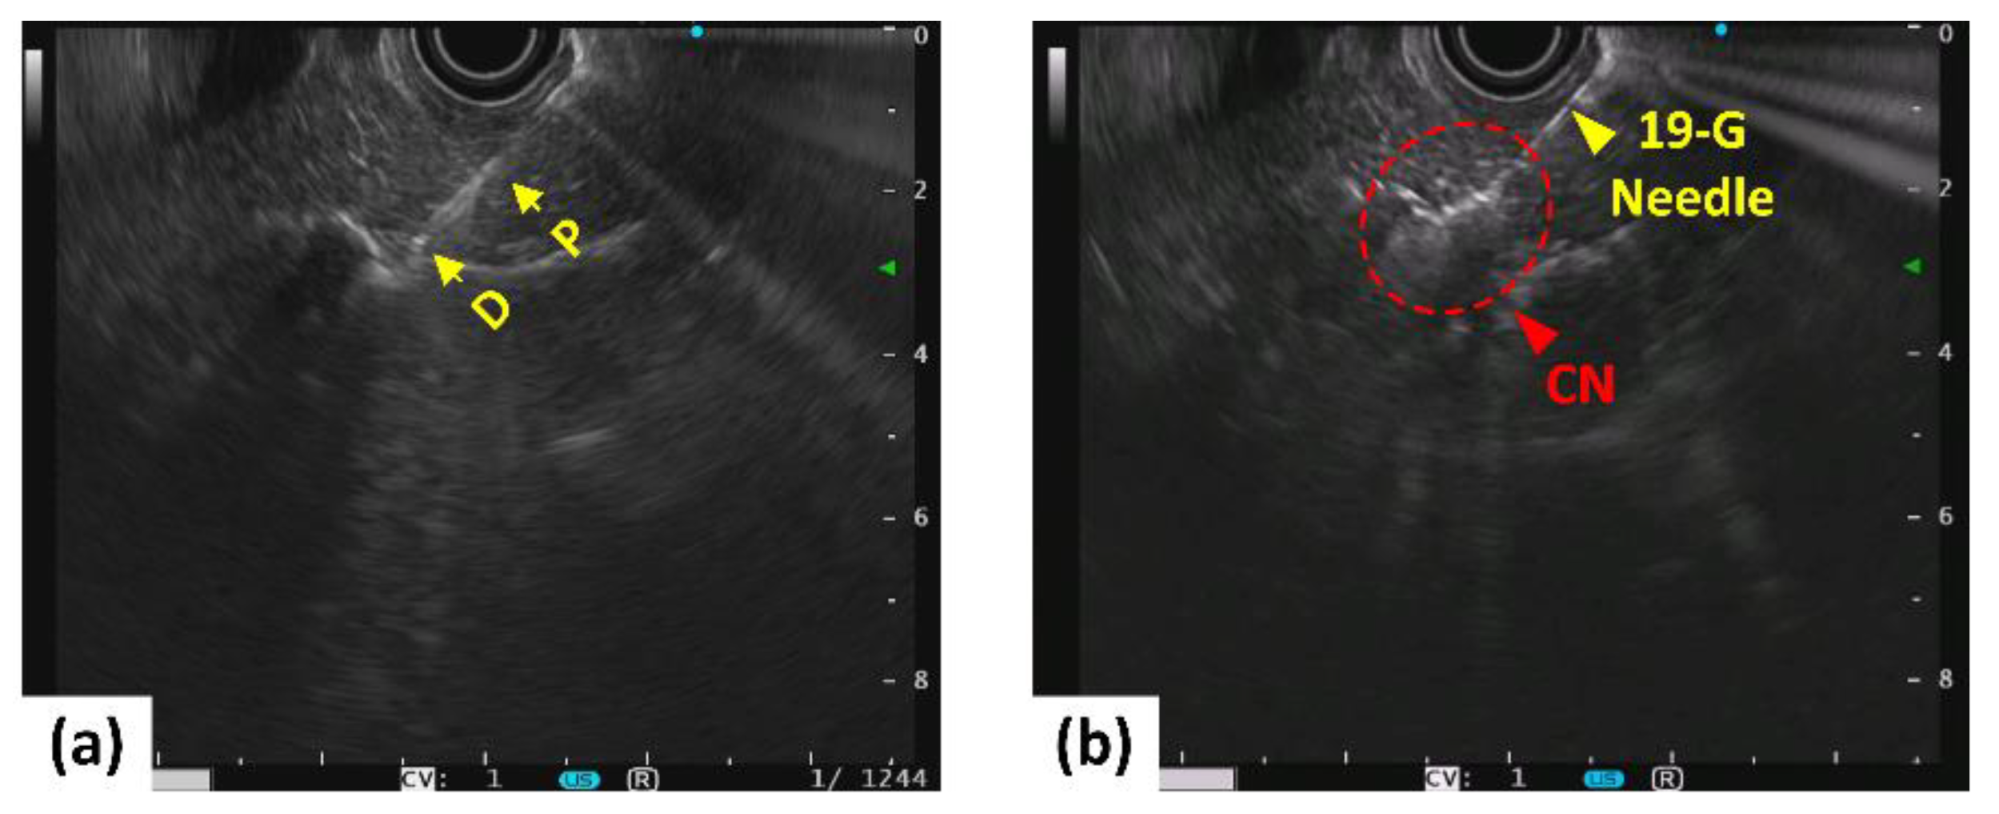

- Truong, V.G.; Jeong, S.; Park, J.-S.; Kim, S.M.; Lee, D.H.; Kang, H.W. Endoscopic ultrasound (EUS)-guided cylindrical interstitial laser ablation (CILA) on in vivo porcine pancreas. Biomed. Opt. Express 2021, 12, 4423–4437. [Google Scholar] [CrossRef]